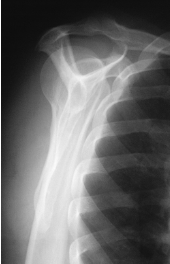

is this a normal or dislocated shoulder? how do you know?

normal, head of humerus superimposed over base of Y